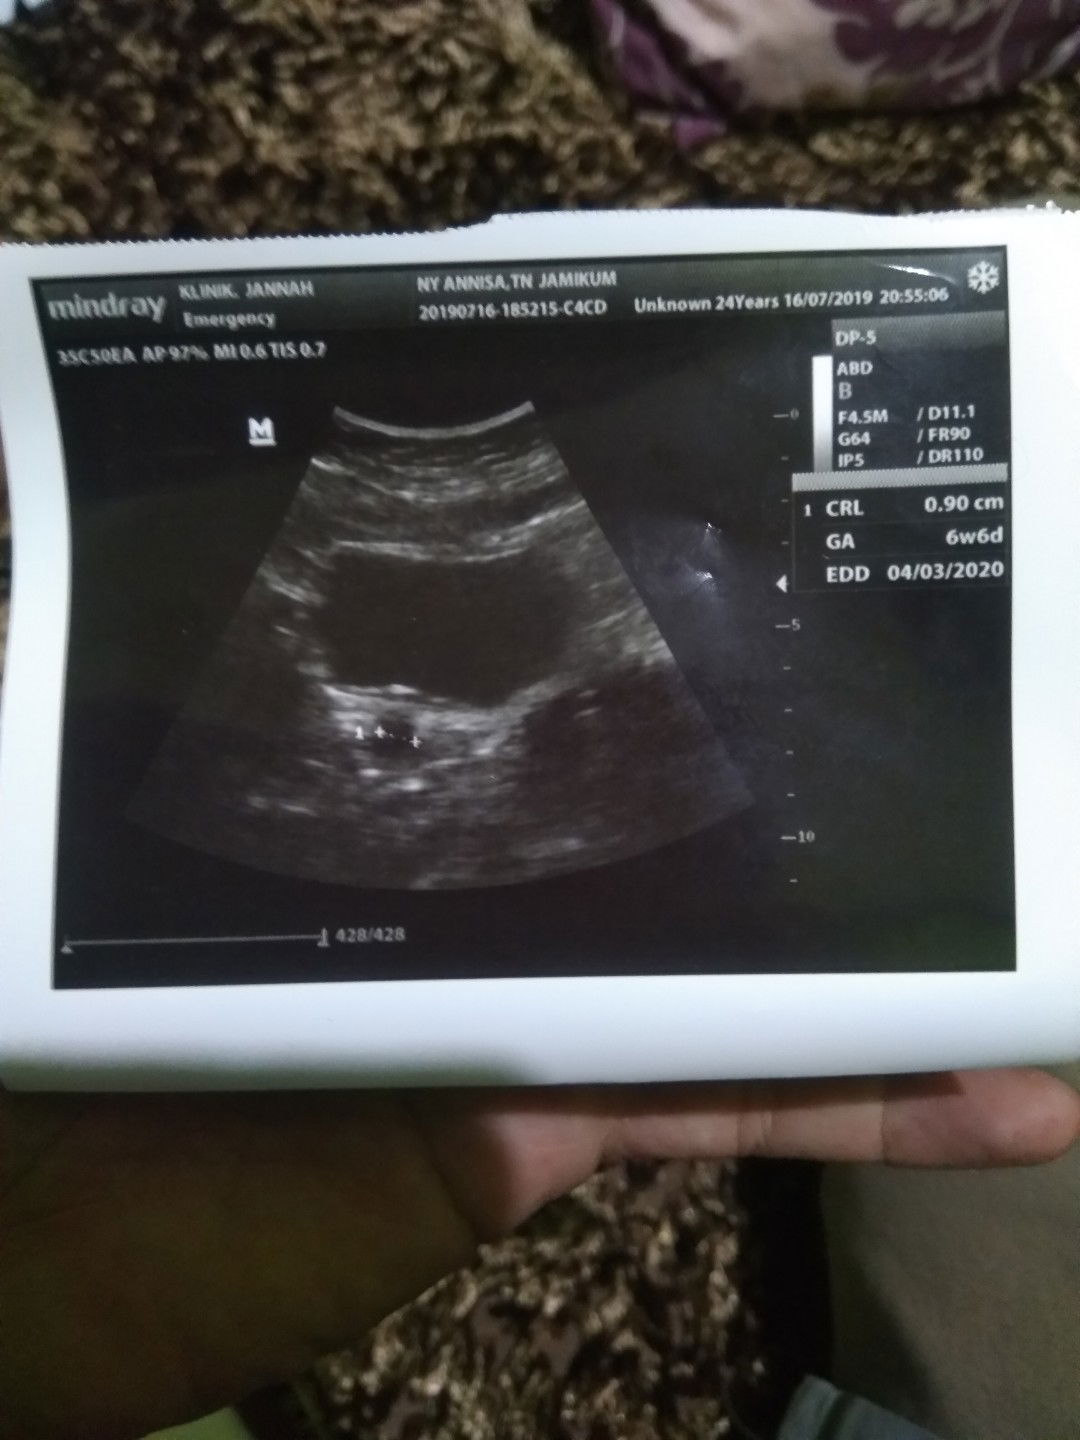

sakit tulang rusuk, dan hasil USG

Minta tolong pak/Bu dokter atau ahli lainnya membaca gambar apakah normal? Terus kemarin sakit punggung, sekarang sakit tulang rusuk, sekarang usia menurut USG 7w1day. Nuhun semuanya???